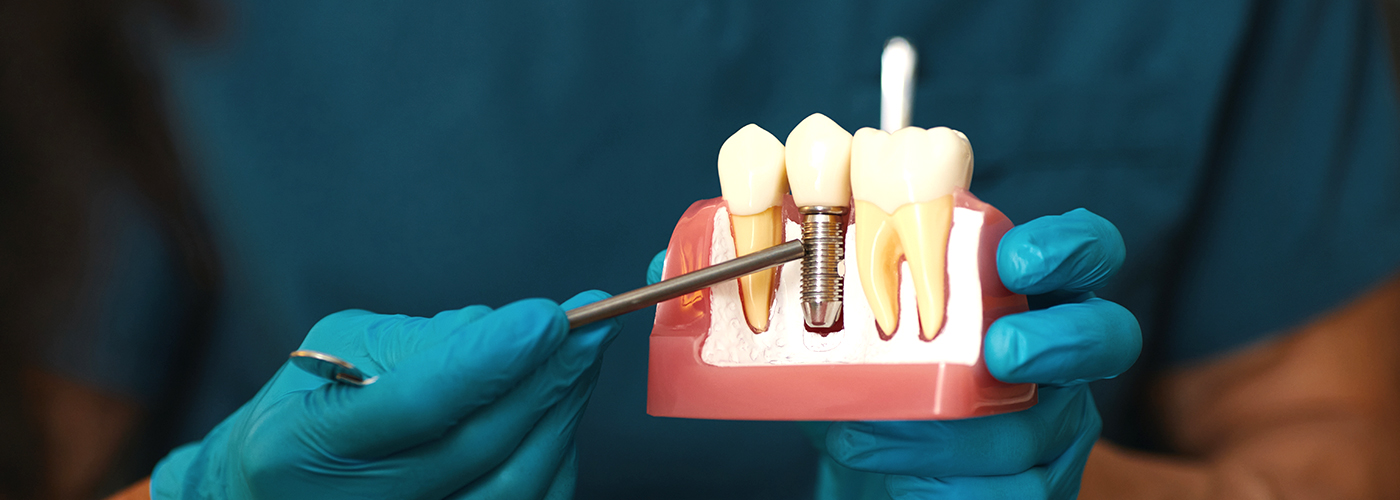

많은 경우 임플란트는 상실된 치아를 대체하는 데 매우 효과적인 치료 방법이 될 수 있습니다.

임플란트는 브리지보다 훨씬 더 영구적인 해결책을 제공하며, 올바르게 관리하면 평생 사용할 수 있습니다.

A플러스치과에서는 전 세계적으로 신뢰받는 프리미엄 브랜드인 스트라우만(Straumann) 임플란트 라인을 사용하고 있으며 스트라우만은 높은 안정성과 장기적인 성공률, 그리고 오랜 임상 경험을 바탕으로 임플란트 분야에서 최고의 품질을 인정받고 있습니다.